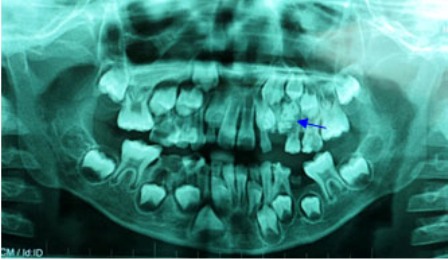

Hình ảnh X-Quang cho thấy túi răng nằm trong miệng bệnh nhi

Bệnh nhi được tiến hành chụp phim X-quang để khảo sát, bác sĩ phát hiện có một khối cản quang ở vùng xương hàm trên bên trái, nằm cạnh khối u là chiếc răng nanh sữa. Qua kết quả trên, bác sĩ chẩn đoán bệnh nhân bị u răng, khối u nằm choán hết đường di chuyển của răng nanh sữa và chắn ngang đường mọc lên của hai răng vĩnh viễn số 3 và số 4.

Bác sĩ đã tiến hành phẫu thuật cắt bỏ khối u xương hàm trên có kích thước 3x3x2cm cho bé. Khối u này gồm nhiều tiểu thể nhỏ kết dính lại với nhau, được bao bọc bằng một bao xơ dày dai chắc. Chia tách u để khảo sát, bác sĩ ghi nhận có tới 54 chiếc răng nhỏ bên trong.